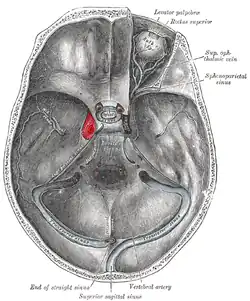

Пеще́ристый си́нус (пеще́ристая па́зуха, также каверно́зный си́нус; лат. sinus cavernosus) — один из синусов твёрдой мозговой оболочки головного мозга. Пещеристый синус является парным и располагается на основании черепа по бокам от турецкого седла; играет важную роль в осуществлении венозного оттока от мозга и глазниц, а также в регуляции внутричерепного кровообращения.

- Клиновидно-теменной синус (лат. sinus sphenoparietalis)

Отток венозной крови из пещеристого синуса в основном направляется по верхнему (впадает в поперечный синус) и нижнему (впадает в сигмовидный) каменистым синусам. Правый и левый пещеристые синусы могут быть соединены между собой передним и задним межпещеристыми синусами (иногда при этом образуется «кольцо», охватывающее турецкое седло со всех сторон).